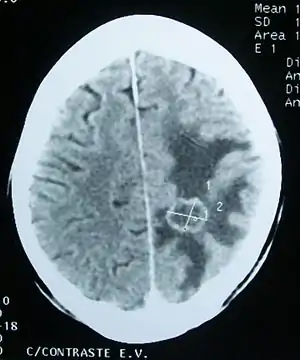

| Edema (darker areas) surrounding a secondary brain tumor. | |